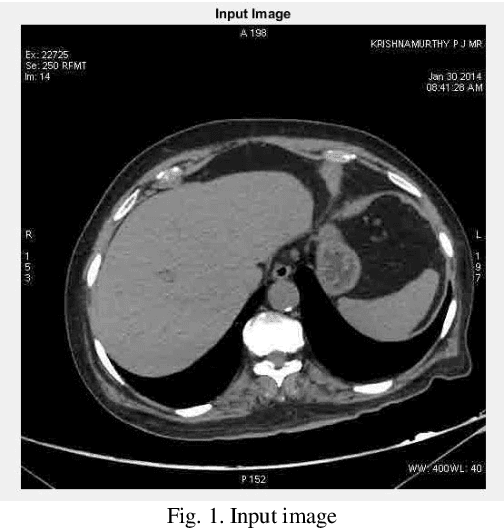

Abstract:Lung cancer is one of the prevalence diseases in the world which cause many deaths. Detecting early stages of lung cancer is so necessary. So, modeling and simulating some intelligent medical systems is an essential which can help specialist to accurately determine and diagnose the disease. So this paper contributes a new lung cancer detection model in CT images which use machine learning methods. There are three steps in this model: noise reduction (pre-processing), segmentation (middle-processing) and optimize segmentation for detect exact are of nodules. This article use some filters for noise reduction and then use Independent Recurrent Neural Networks (IndRNN) as deep learning methods for segmentation which optimize and tune by Genetic Algorithm. The results represented that the proposed method can detect exact area of nodules in CT images.